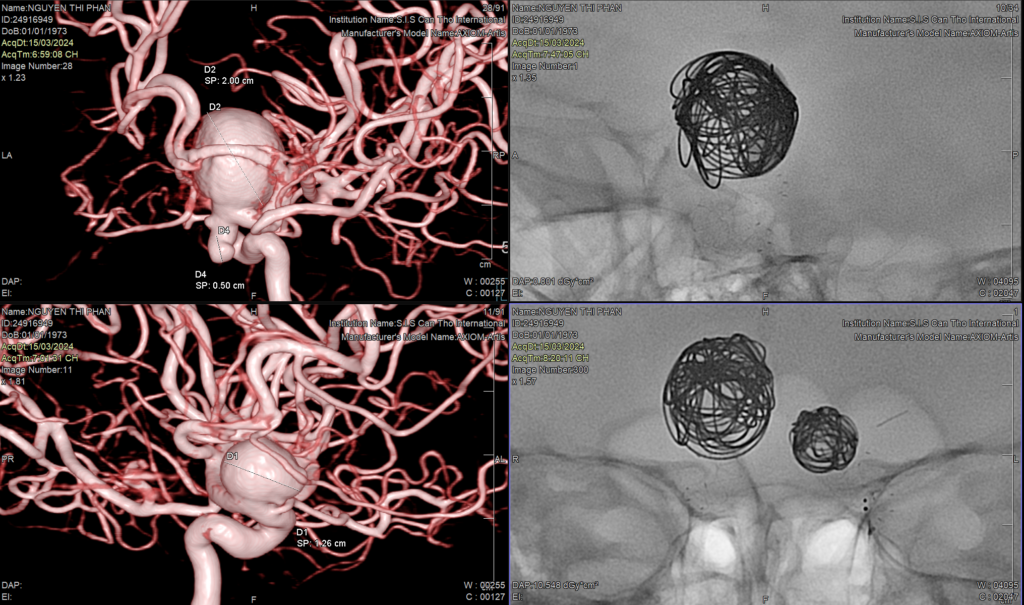

Tối qua (15/3), sau gần 2 giờ can thiệp, các bác sĩ Bệnh viện ĐKQT S.I.S Cần Thơ đã can thiệp nội mạch đặt Stent chuyển dòng và Coils thành công cho 3 túi phình: bên phải 2 túi và bên trái 1 túi, của chị Phận.

Tuy nhiên, trong quá trình chụp DSA tại S.I.S nhờ công nghệ dựng hình mạch máu 3D trên máy DSA hiện đại ICONO, các bác sĩ phát hiện bệnh nhân có thêm túi phình thứ 3 nằm cạnh túi phình khổng lồ bên phải với kích thước to nhất 20mm, 12mm và 5mm”.

Sau chưa đầy 2 giờ, rất may các bác sĩ đã “khóa ngòi” được 3 “quả bom” phình mạch với một mức kinh phí… 0 đồng cho 2 stent trị giá hơn 400 triệu nhờ vào sự giúp đỡ của quý mạnh thường quân trong ngoài nước và tập thể y bác sĩ, cán bộ công nhân viên bệnh viện đóng góp.